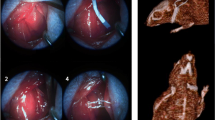

In addition, VNS affected cerebral vascular regeneration. Male Sprague‒Dawley rats with focal cerebral ischaemia/reperfusion (I/R) injury had less severe neuronal damage in the penumbral area, which was correlated with increased microvessel density. The increase in endothelial cells with proliferating cell nuclear antigen PCNA/CD31 (two biomarkers of vascular proliferation) double staining can clarify this view [51]. In a similar study using I/R rats, the level of growth differentiation factor 11 (GDF11), a proliferation factor of brain capillary endothelial cells, was significantly increased after VNS in the ischaemic region, as well as in the plasma [52]. Additionally, the protective effects of VNS on vascular endothelial cells were found to be correlated with reduced activation of the NF-κB pathway [53]. Ovariectomized (OVX) rats were treated with chronic VNS, and inhibition of the translocation of NF-κB/p65 to the cell nucleus was observed in vascular endothelial cells by immunohistochemistry. Moreover, the results of light microscopy and electron microscopy showed that chronic VNS could prevent endothelial swelling, desquamation and even necrosis. This further demonstrated that chronic VNS could protect the vascular endothelium by inhibiting the inflammatory reaction mediated through the NF-κB/p65 pathway.